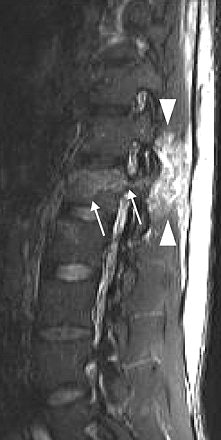

| Inversion-recovery sagittal MR images of lumbar spine in 31-year-old man. Chance fracture of L1 shows marked high signal in interspinous ligaments and soft tissues (arrowheads). Bone marrow edema (arrows) is seen in pedicle and vertebral body. |

MR showed marked soft-tissue damage through the posterior elements and surrounding soft tissues in all patients. "MRI evaluation provides information regarding the integrity of the posterior and middle-column ligaments, annulus fibrosis, and spinal cord in neurologically injured patients," they added.